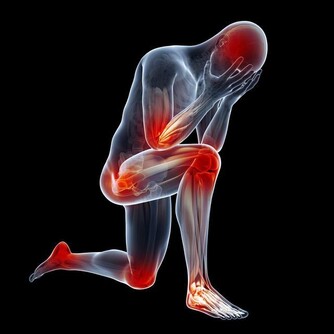

過度勞累會對您的身心健康產生深遠的負面影響。無論是背痛,沮喪,心臟問題,肥胖症,還是經常生病,都要考慮工作是否是原因。您會知道過度勞累何時會影響您的健康,並且您將不得不決定是否值得這樣做。